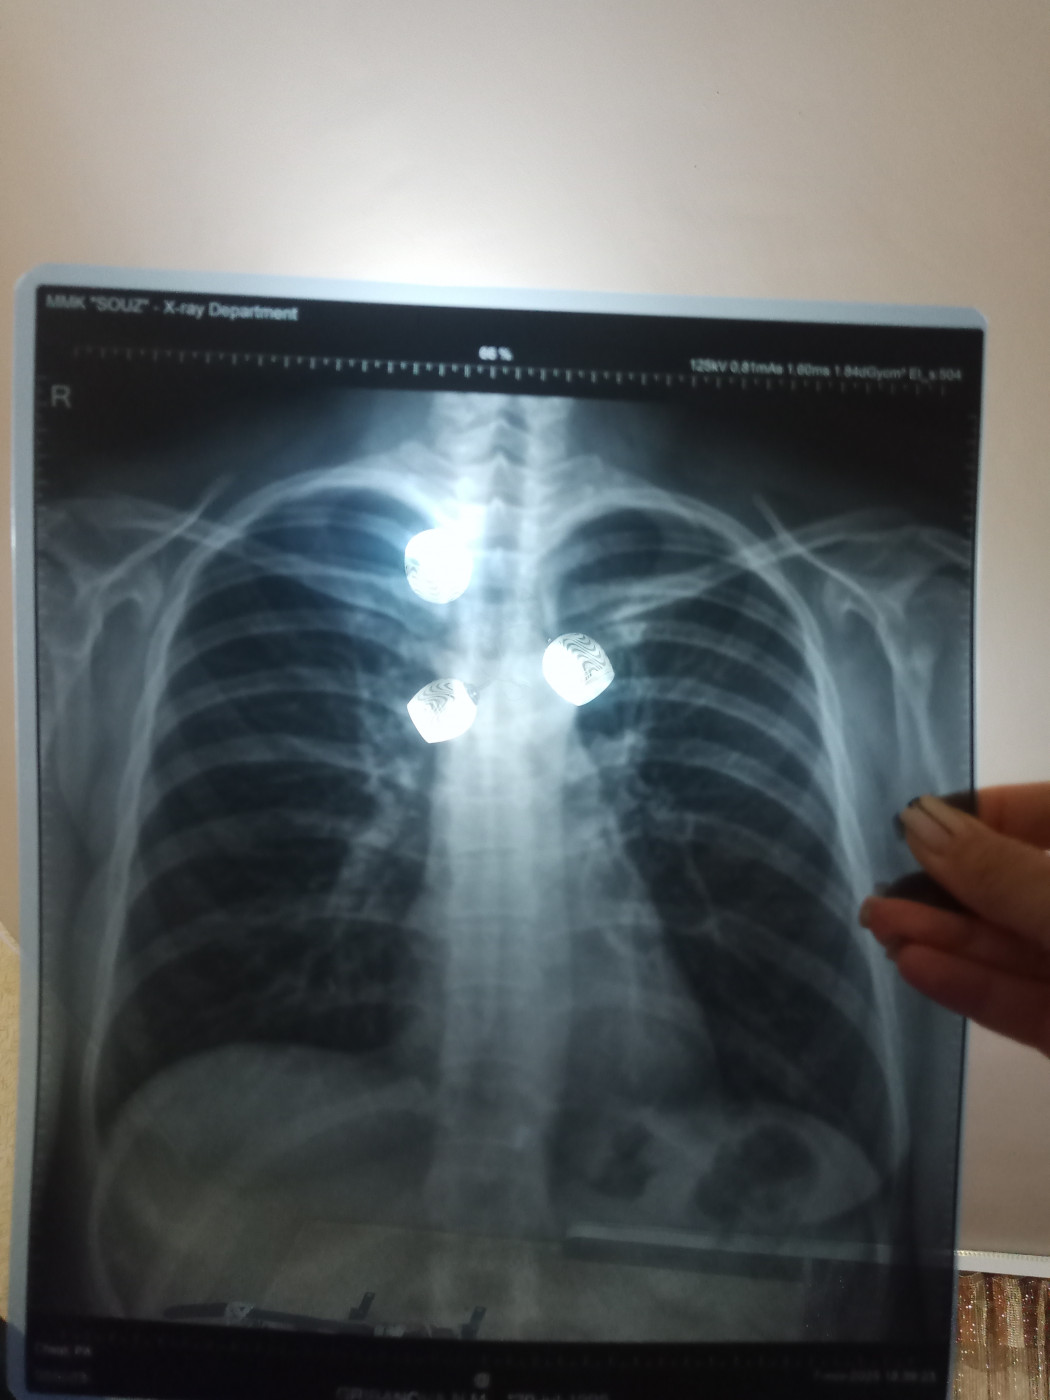

Рентген груди